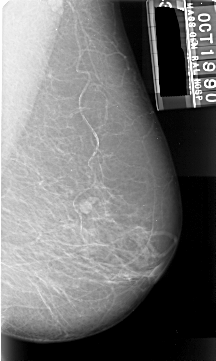

A_1006_1.LEFT_CC

LEFT_CC LINES 5416 PIXELS_PER_LINE 2866 BITS_PER_PIXEL 16 RESOLUTION 42 OVERLAY

FILE: A_1006_1.LEFT_CC.OVERLAY

TOTAL_ABNORMALITIES 1

ABNORMALITY 1

LESION_TYPE MASS SHAPE IRREGULAR MARGINS ILL_DEFINED

ASSESSMENT 4

SUBTLETY 5

PATHOLOGY MALIGNANT

TOTAL_OUTLINES 1

BOUNDARY